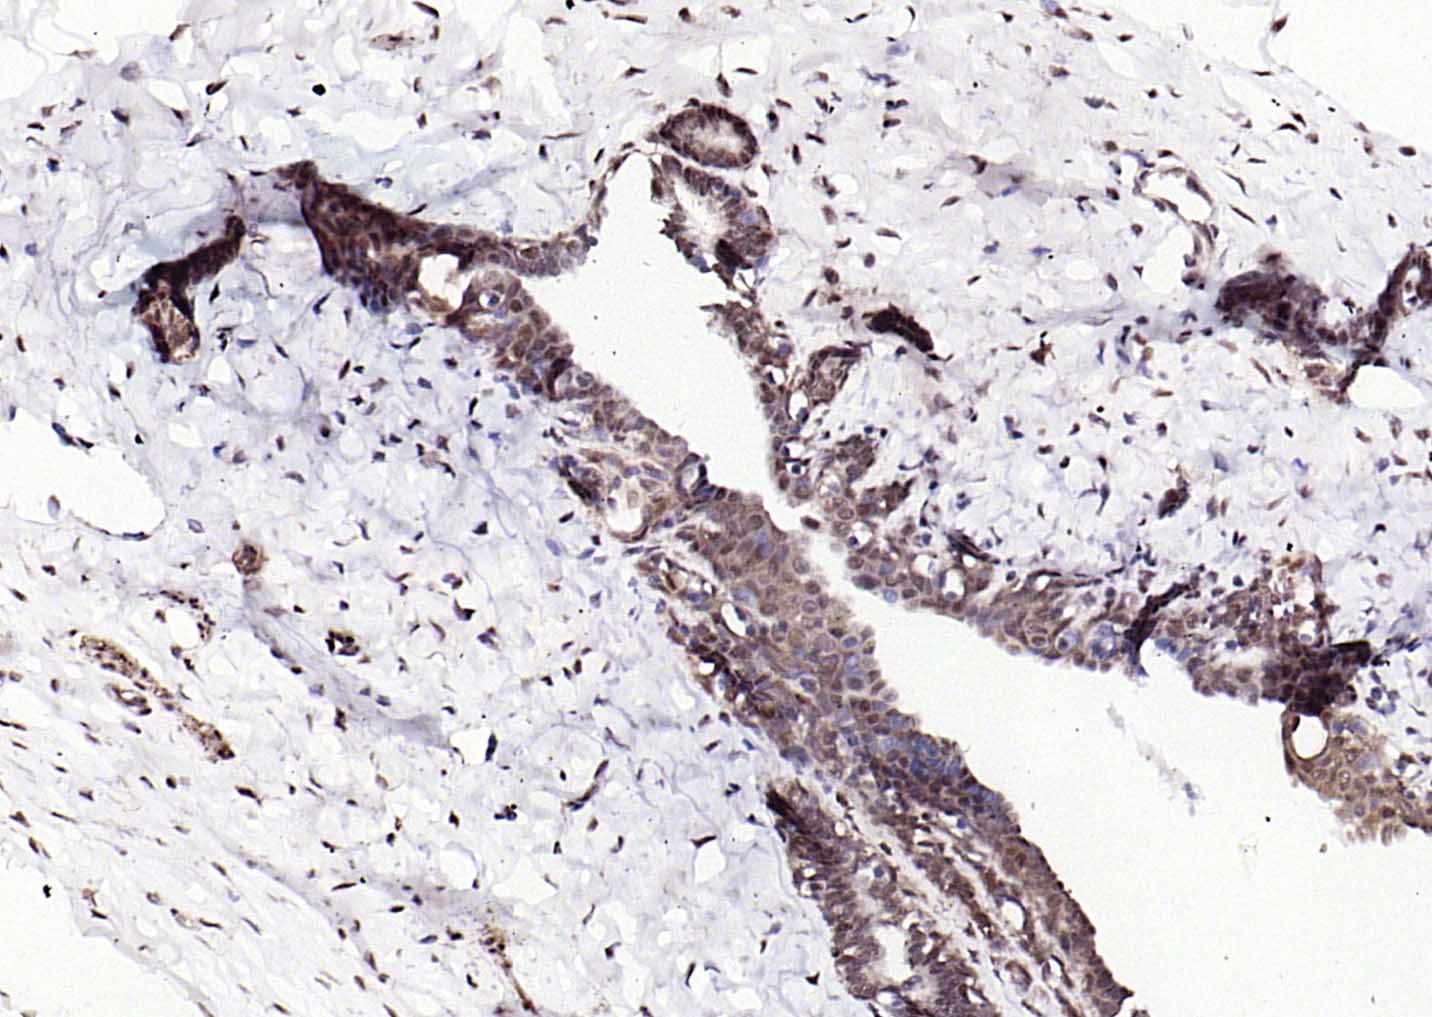

Paraformaldehyde-fixed, paraffin embedded Human Breast; Antigen retrieval by boiling in sodium citrate buffer (pH6.0) for 15 min; Antibody incubation with ESR2 Polyclonal Antibody, Unconjugated (bs-0116R) at 1:200 overnight at 4°C, followed by conjugation to the SP Kit (Rabbit, SP-0023) and DAB (C-0010) staining.

Paraformaldehyde-fixed, paraffin embedded Rat Breast; Antigen retrieval by boiling in sodium citrate buffer (pH6.0) for 15 min; Antibody incubation with ESR2 Polyclonal Antibody, Unconjugated (bs-0116R) at 1:200 overnight at 4°C, followed by conjugation to the SP Kit (Rabbit, SP-0023) and DAB (C-0010) staining.